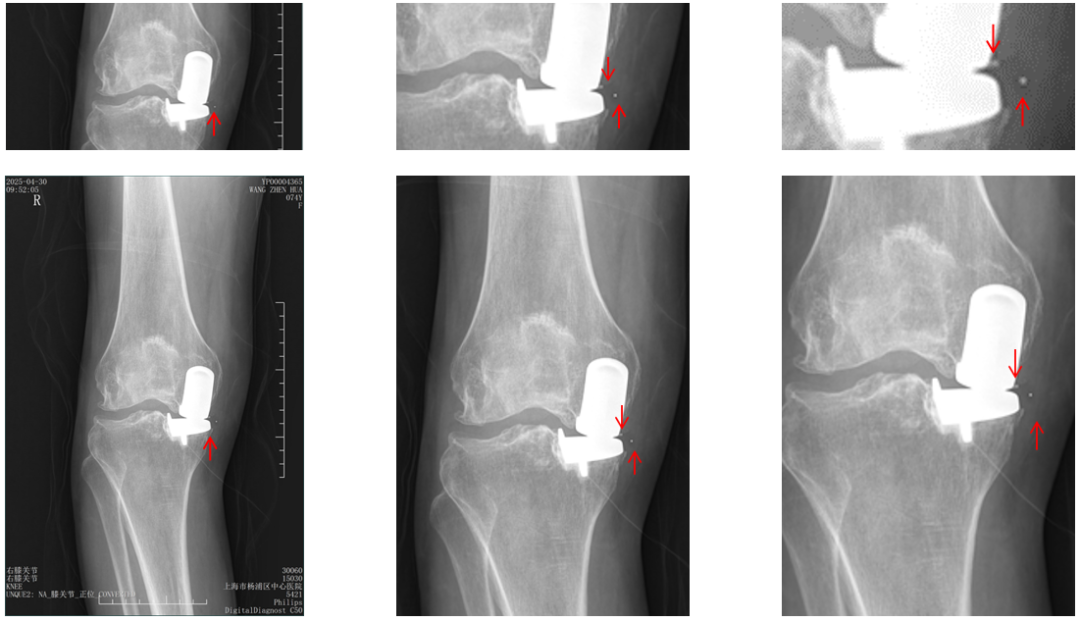

病例展示1

病例1:Bearing 前脱位

病例1:Bearing 前脱位的处理

病例展示2

病例2:Bearing 破裂( X-ray正位)

解读:两个点都在内侧

病例2:Bearing 破裂( X-ray侧位)

解读:股骨假体与胫骨假体间隙还存在,在图像放大4倍情况下,才依稀看到模糊的点.

病例2:Bearing 破裂

病例2:Bearing 破裂的处理